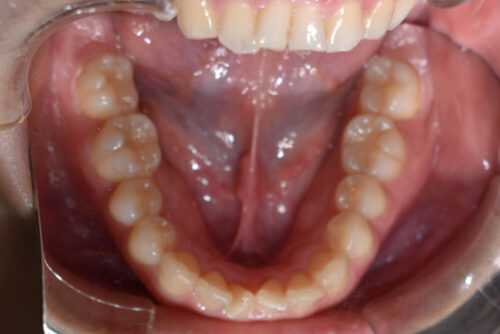

ワイヤー矯正治療10か月後です。

かみ合わせをあげながら

歯の並びをそろえていくことで

歯をぬかなくても

出っ歯にならずに

非抜歯矯正治療で

咬合させることができます。